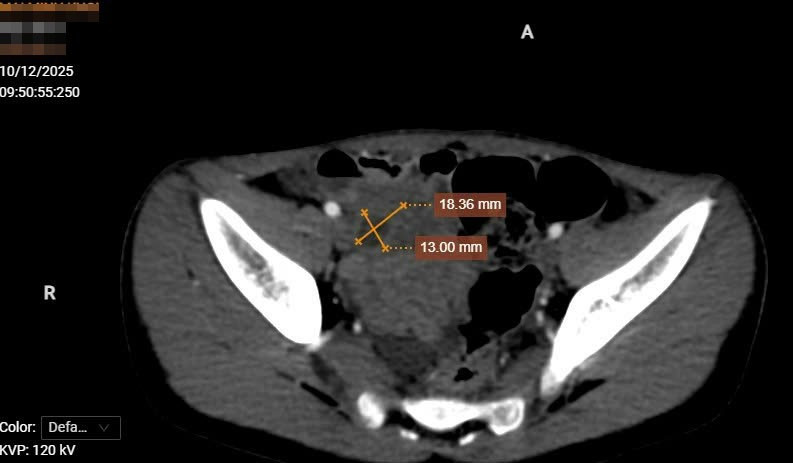

Sau khi bệnh nhân được siêu âm và cắt lớp vi tính thấy: Hố chậu phải có cấu trúc dạng dịch, thành của cấu trúc này có các lớp giống với các lớp của thành ống tiêu hóa, ngấm thuốc mạnh sau tiêm. Dịch bên trong cấu trúc này không đồng nhất. Thành của cấu trúc này có vị trí mất liên tục, thâm nhiễm xung quanh.

Ngay lúc này, bệnh nhân được hội chẩn liên chuyên khoa bởi các bác sĩ Chẩn đoán hình ảnh, Ngoại tổng hợp, Gây mê hồi sức. Bệnh nhân được chẩn đoán viêm phúc mạc khu trú hố chậu phải nghĩ đến nguyên nhân do nang ruột đôi vỡ. Các bác sĩ đã thống nhất thực hiện phẫu thuật mổ cấp cứu cho bệnh nhân.